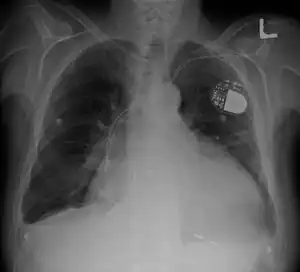

Cardiomegaly on chest X-ray with a pacemaker

• Chest X-Ray: X-ray images help see the condition of the lungs and heart. If the heart is enlarged on an X-ray, other tests will usually be needed to find the cause. A useful measurement on X-ray is the cardio-thoracic ratio, which is the transverse diameter of the heart, compared with that of the thoracic cage."[24] These diameters are taken from PA chest x-rays using the widest point of the chest and measuring as far as the lung pleura, not the lateral skin margins. If the cardiac thoracic ratio is greater than 50%, pathology is suspected, assuming the x-ray has been taken correctly.[25] The measurement was first proposed in 1919 to screen military recruits. A newer approach to using these x-rays for evaluating heart health takes the ratio of heart area to chest area and has been called the two-dimensional cardiothoracic ratio.[26]